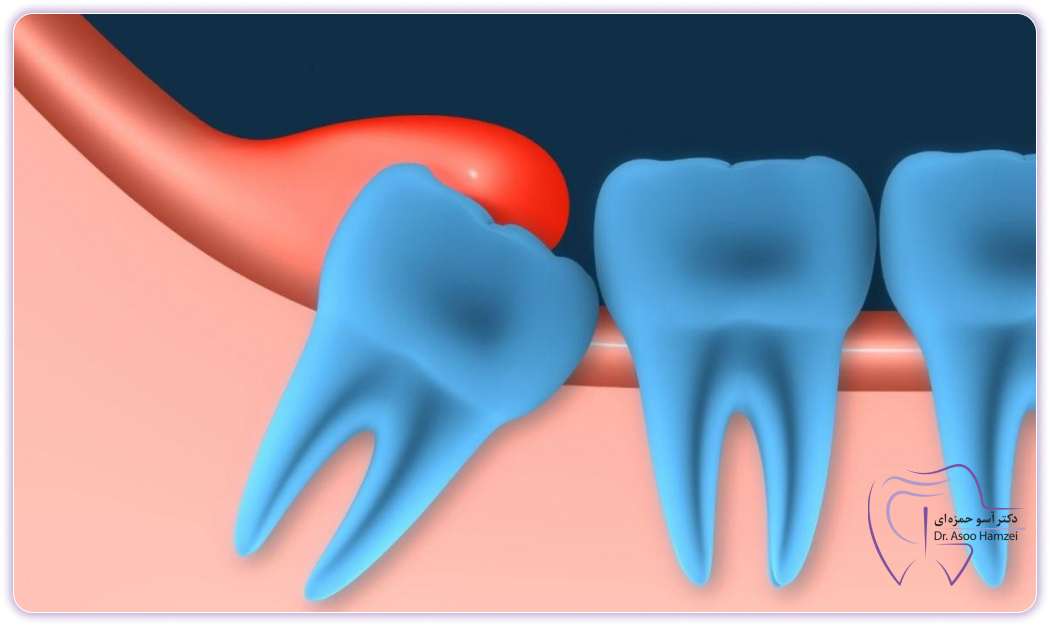

If your wisdom teeth are impacted or partially impacted, that is, they have not erupted from the gums or if half of them have erupted from the gums, they can create a source and a place for the accumulation of bacteria and food. In this case, these bacteria accumulate around the wisdom tooth and can eventually cause a wisdom tooth abscess or wisdom tooth abscess. If this infection is not treated, it can cause many problems and even transfer the infection into the blood and cause risks such as blood infection or even worse, so it is suggested to go to the dentist as soon as possible to treat the infection.

Wisdom tooth abscess in adults usually occurs when the soft tissues around the wisdom tooth, especially If the tooth is partially embedded or embedded, they will suffer from inflammation and accumulation of bacteria. This infection is known as perichronitis and causes pain, swelling, redness and may discharge pus and bad breath. Factors such as improper growth of wisdom teeth, accumulation of bacteria and lack of oral hygiene can lead to this type of infection, which may lead to more serious problems if left untreated.